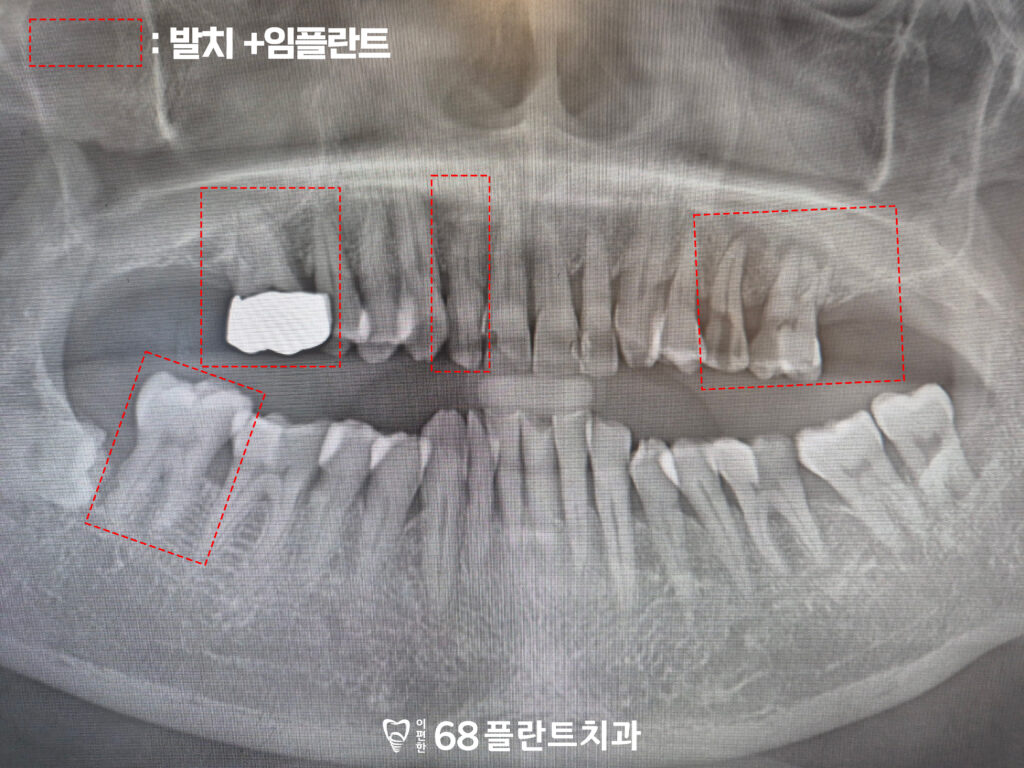

19.11.20

위 환자분은

씹을 때마다 치아가 불편하고

상실된 부위도 있어

전체적으로 식사하기 힘들다며

철산역치과 이편한68플란트에

내원해 주셨습니다.

확인해 보니,

치아가 마모가 되어있는 부위도 있었으며

뿌리 끝 염증이 생겨있는 것도

확인할 수 있었습니다.

또한 위쪽 끝 어금니가 상실되어 있어,

오랜 기간 동안 씹는 힘의 균형이 무너지다 보니

맞닿는 아래쪽 어금니가 서서히

위 방향으로 솟아오르는 정출 현상까지

진행된 상태였습니다.

그래서 해당 부위들은 발치 진행 후

임플란트를 식립 하기로 하였습니다.